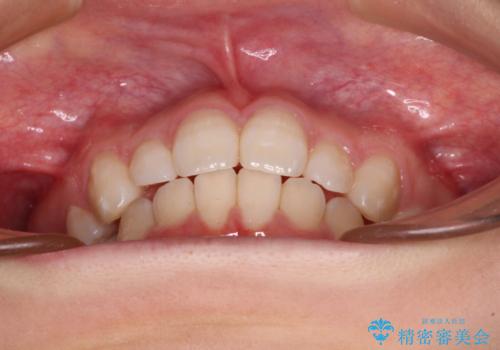

抜歯矯正の後戻り インビザライン・ライトによる矯正治療

治療途中、妊娠・出産があり、1年近く治療が停滞しましたが、無事に終了することができました。

インビザライン・ライトは提供されるマウスピースの数に制限があり、通常のタイプよりもマウスピース提供期間が短くなっている一方、安価に治療を行うことができるプランです。

治療のゴールも変更できないため、軽微な歯列不正や、後戻り改善などに適しています。